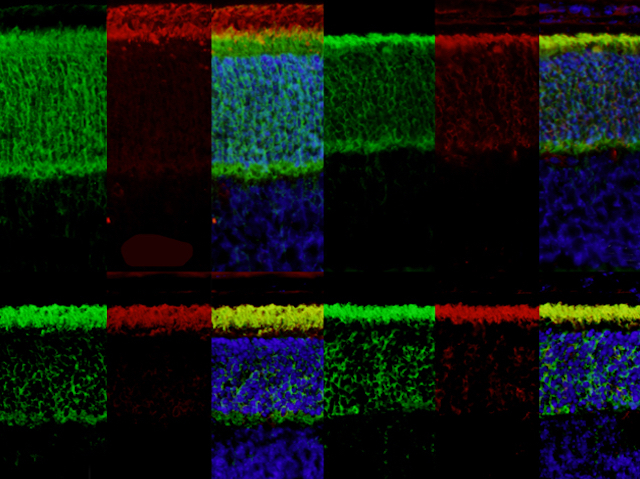

Bardet-Biedl syndrome (BBS) is a complex disease. More than 15 inherited gene changes have been implicated in the condition, and it affects sight, smell, growth, behaviour, and more. These problems all come down to faults in cilia – tiny sensory hairs on the surface of cells. One place that’s packed with cilia is the retina at the back of the eye, which senses light, so it’s unsurprising that people with BBS have sight problems. These images show slices from the retina of mice, with the distinct layers highlighted with different coloured stains. The top left three panels are from a healthy animal, while the other sets of images are from animals with genetic faults linked to BBS, which haven’t properly formed the layers in the retina. By figuring out what’s gone wrong in these cells, researchers hope to gather new clues to understand BBS and develop ways to save patients’ sight.